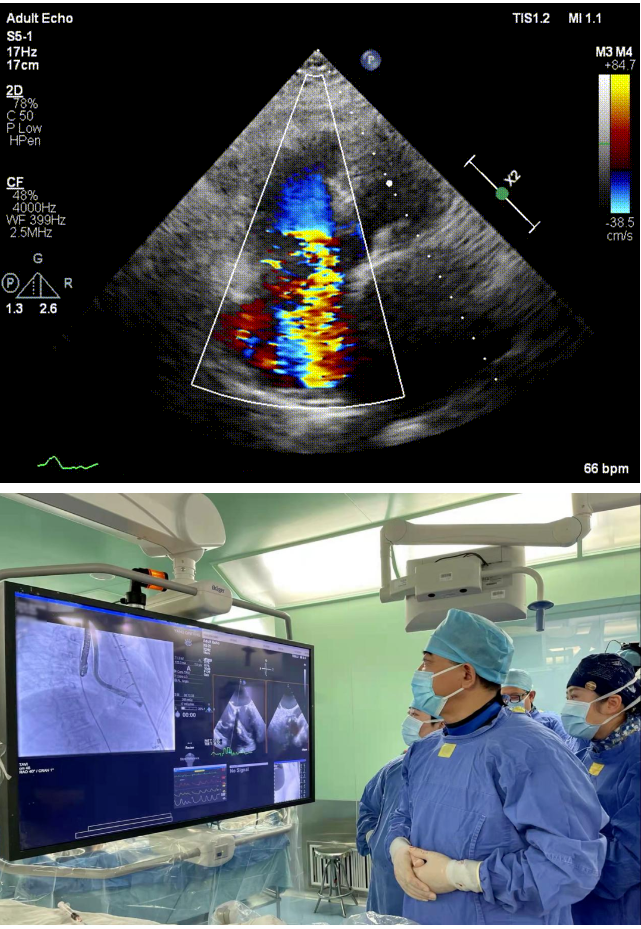

本次接受治療的患者是一名74歲的女性,14年前因風(fēng)濕性心臟病行二尖瓣生物瓣植入術(shù),合并房顫。近3年來反復(fù)因腹脹、納差、下肢水腫入院,藥物治療欠佳。心臟超聲顯示三尖瓣極重度反流(有效反流口面積:0.76cm²,反流容積:79ml),繼發(fā)性右房室增大及上、下腔靜脈增寬(右房上下徑*左右徑:52*41mm,右室左右徑:46mm,下腔靜脈:29mm),右室收縮功能正常,肺動脈收縮壓 43mmHg,左心室射血分?jǐn)?shù)73% 。患者既往開胸手術(shù)史,術(shù)前評估STS 評分為7.02分,CRS 9分,無法接受體外循環(huán)下三尖瓣外科手術(shù)。面對這一傳統(tǒng)治療無法解決的困境,葛均波院士及其團(tuán)隊周達(dá)新教授、潘文志教授、張源博士、陳莎莎博士及心超室的潘翠珍教授、李偉教授經(jīng)過討論決定,采用創(chuàng)新的Lux-Valve Plus系統(tǒng)為患者進(jìn)行經(jīng)血管三尖瓣置換。

手術(shù)在患者全麻狀態(tài)下進(jìn)行,采用經(jīng)右側(cè)頸靜脈作為入路,將裝載有人工瓣膜的輸送器緩慢推送至右心房;并在經(jīng)食道超聲和DSA的引導(dǎo)下小心調(diào)整輸送器角度,將輸送器送入右心室;逐步釋放瓣膜錨定裝置和盤片,調(diào)整瓣膜位置后,錨定瓣膜完成植入。術(shù)后右房壓明顯下降,從術(shù)前的25/10(16) mmHg降至術(shù)后即刻的12/7(10) mmHg,術(shù)后超聲提示人工三尖瓣同軸性良好,固定牢固,無反流及瓣周漏,手術(shù)室即刻拔除氣管插管。